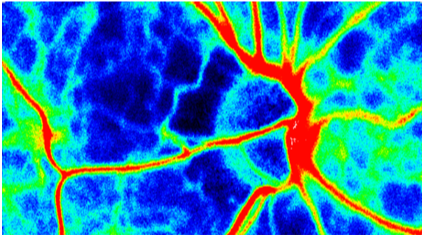

緑内障においては視神経乳頭血流が低下することが知られています。非侵襲的な血流測定方法としてはLaser Dopplerなどが用いられてきましたが、近年では、より正確性・再現性に優れたLaser Speckle FlowgraphyLSFG)を用いた手法が開発されています。

LSFGでは眼底にダイオード光を照射し、それが赤血球に反射し、反射光が互いに干渉しあい形成されたスペックルパターンの変化率を計測し、血流波形・血流速度・血流量を測定します。血流波形の形状から血流の安定性を示すパラメータや血管抵抗を示すパラメータなど様々なパラメータを算出することができます。

スペックルパターンの変化率が高い部位が暖色系、低い部位が寒色系で示されています。特に血管走行に沿って暖色系の部位が広がっており、血流が多い部位が暖色系で示されていることが分かります。逆に血管が少ない部位は寒色系となっており、血流が少ない部位が寒色系で示されております。